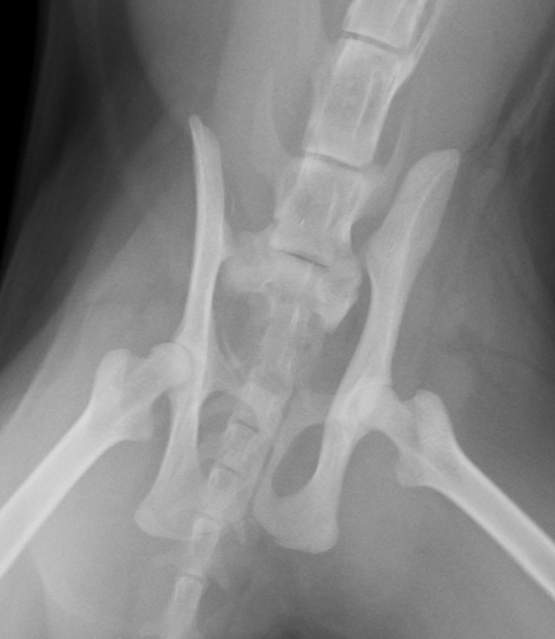

X 線を見せていただいたところ、骨盤の仙腸関節が左右で脱臼していることが判明、不幸中の幸いでしょうか、ほかの骨折は見当たりませんでした。数日間体調を確認してから、手術を行いました。腰の左右2ヶ所から整復した骨を無事留めることができました。仙骨というしっぽの付け根に当たる骨(中に太い神経が走っています)を、骨盤に左右からスクリューで留めることは、本来難しい手技ですが、今回はきれいに入れることができました。仙骨付近は、神経の分岐部が多くあるため、その後排尿障害や後枝麻痺など後遺症が残ることもあります。

数日して自宅安静で退院となりましたが、その際診察台からキャリーケースに普通に歩いていったのをみて、安心しました。今後は、室内で飼育していただけることになったので、こういった怪我もしなくなると思います。自宅のトイレでおしっこもできました。よかったね、ダヤンちゃん!

来院時、痛くてかなり鳴いていました・・・仙骨と骨盤が外れています。 | 左右からスクリューとピンで留めました。かなり安定して、痛みも数日でなくなったことでしょう。 |